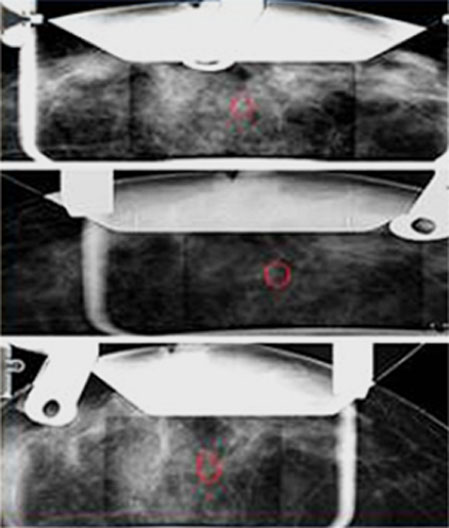

Calcification clusters are concentrated in the close to the chest wall from the center of nipple

After insertion of Vacuum Probe, Reconfirmation the exact needle positioning

Confirmation of the decrease of calcification around the vacuum probe after sampling